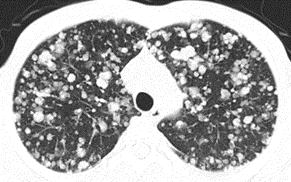

Tomografia computerizată toracică (CT toracic): este mult mai specifică decât radiografia, fiind capabilă să detecteze chiar și leziuni de mici dimensiuni(de câțiva milimetri) și să faciliteze diagnosticul încă din stadiile incipiente ale bolii. CT cu substanță de contrast constituie investigația imagistică de elecție pentru diagnosticul cancerului pulmonar. Administrarea acestei substanțe de contrast permite uneori deosebirea între masele tumorale maligne(canceroase) și cele benigne(ne-canceroase) cât și o mai bună delimitare a structurilor anatomice și a gradului de invazie a tumorii. Poate fi utilă și în excluderea altor patologii pulmonare cât și pentru stadializarea cancerului(în funcție de localizare, de dimensiunea masei tumorale, de prezența unor adenopatii(creșterea în volum a ganglionilor limfatici) sau a metastazelor pulmonare. Trebuie ținut cont că, această investigație presupune o doză importantă de radiație, astfel încât, este indicată doar în prezența unui tablou clinic și a unei radiografii toracice care a ridicat deja suspiciunea unui cancer.

Tomografia cu emisie de pozitroni(PET-CT) este o metodă imagistică modernă care, prin intermediul unei substanțe de contrast speciale(glucoză marcată radioactiv), evaluează activitatea metabolică a țesuturilor din întregul organism. Formațiunile maligne au un consum crescut de glucoză comparativ cu țesuturile sănătoase, astfel încât, pot fi ușor depistate prin această investigație. Este deosebit de utilă în depistarea metastazelor sau în evaluarea unor noduli suspecți. Însă, nu trebuie efectuată de rutină ci se adresează în special pacienților la care s-a stabilit deja diagnosticul de neoplasm printr-o biopsie.